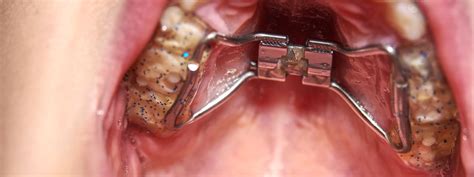

El disyuntor de paladar se trata de un aparato fijo, que dependiendo de la edad, cementado con bandas en los molares o fijado con microtornillos.

Es un novedoso sistema que sujeta el disyuntor palatino directamente en el hueso del paladar, que recibe las fuerzas de apertura del aparato.